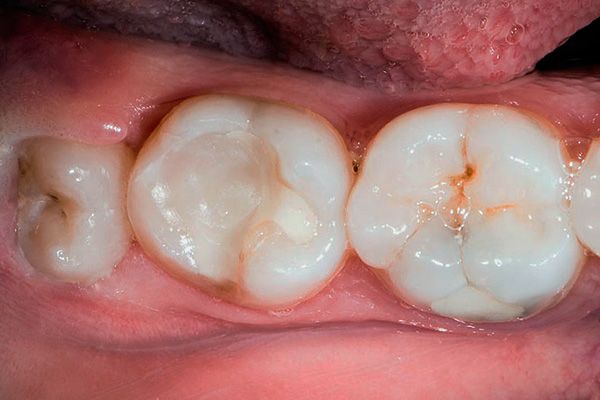

Foto di un dente semi-artificiale di saggezza: